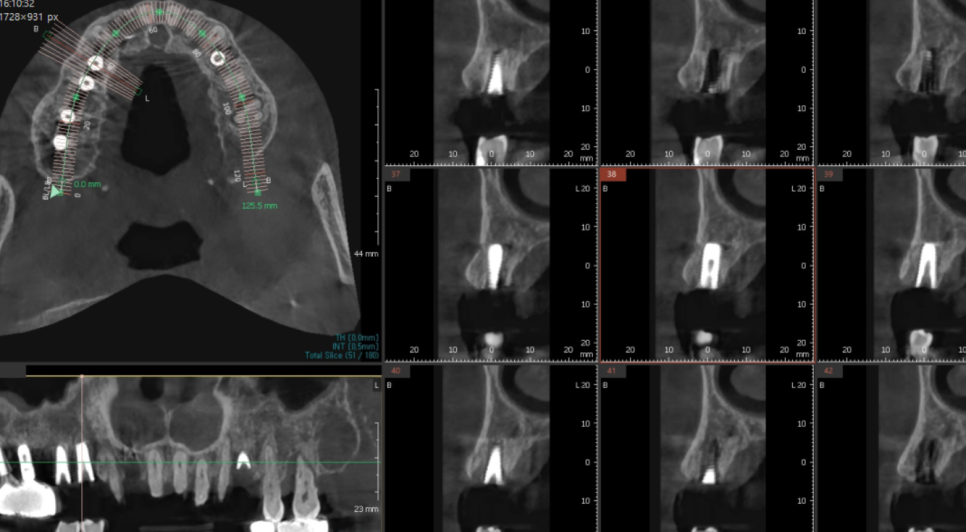

미리 CT를 통하여

식립 예정 부위를 분석하였기 때문에

하루에 다수 치아 수술이 가능했습니다.

강일동 임플란트 10개 식립

문제 없이 끝내드렸습니다 .